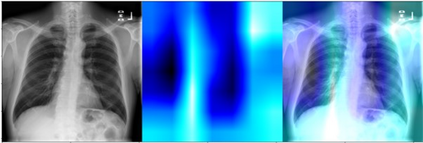

Deep learning (DL) analysis of Chest X-ray (CXR) and Computed tomography (CT) images has garnered a lot of attention in recent times due to the COVID-19 pandemic. Convolutional Neural Networks (CNNs) are well suited for the image analysis tasks when trained on humongous amounts of data. Applications developed for medical image analysis require high sensitivity and precision compared to any other fields. Most of the tools proposed for detection of COVID-19 claims to have high sensitivity and recalls but have failed to generalize and perform when tested on unseen datasets. This encouraged us to develop a CNN model, analyze and understand the performance of it by visualizing the predictions of the model using class activation maps generated using (Gradient-weighted Class Activation Mapping) Grad-CAM technique. This study provides a detailed discussion of the success and failure of the proposed model at an image level. Performance of the model is compared with state-of-the-art DL models and shown to be comparable. The data and code used are available at https://github.com/aleesuss/c19.